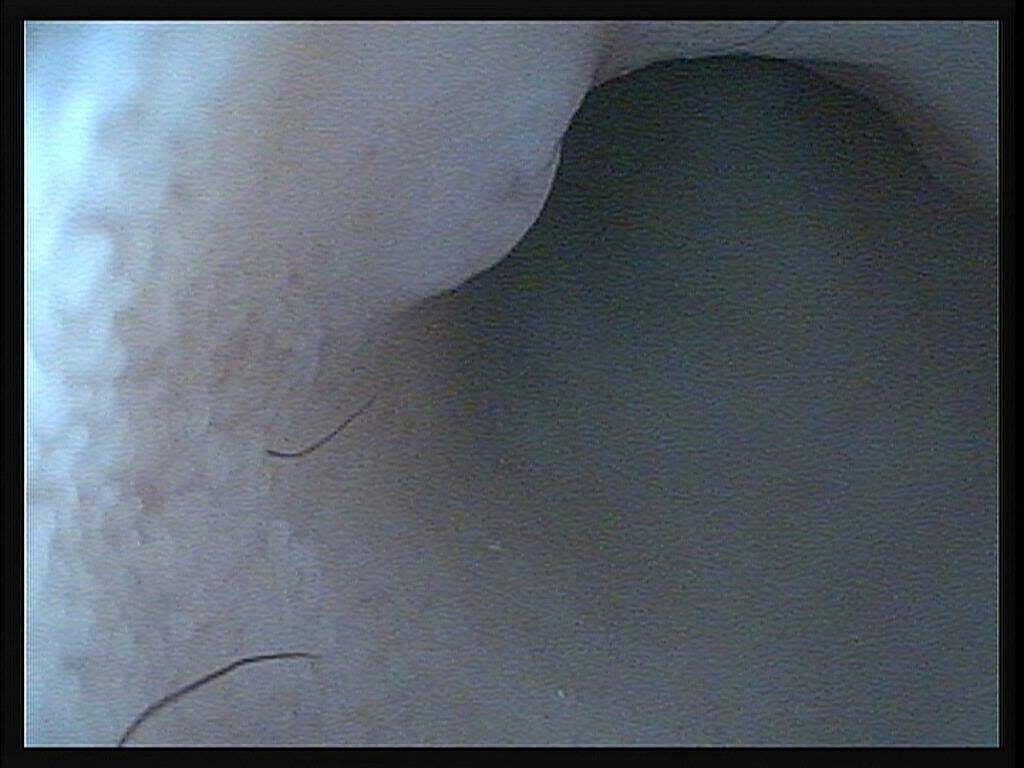

檢查的過程中,醫師並沒有發現麵滷的腸胃有任何異狀,

只有在裡面發現一坨毛球,其餘並無大礙。

醫師幫麵滷看完胃視鏡後說明,

麵滷的腸胃裡面只有看到一些雜毛,腸胃本身並無大礙,

不進食可能是其他原因造成。